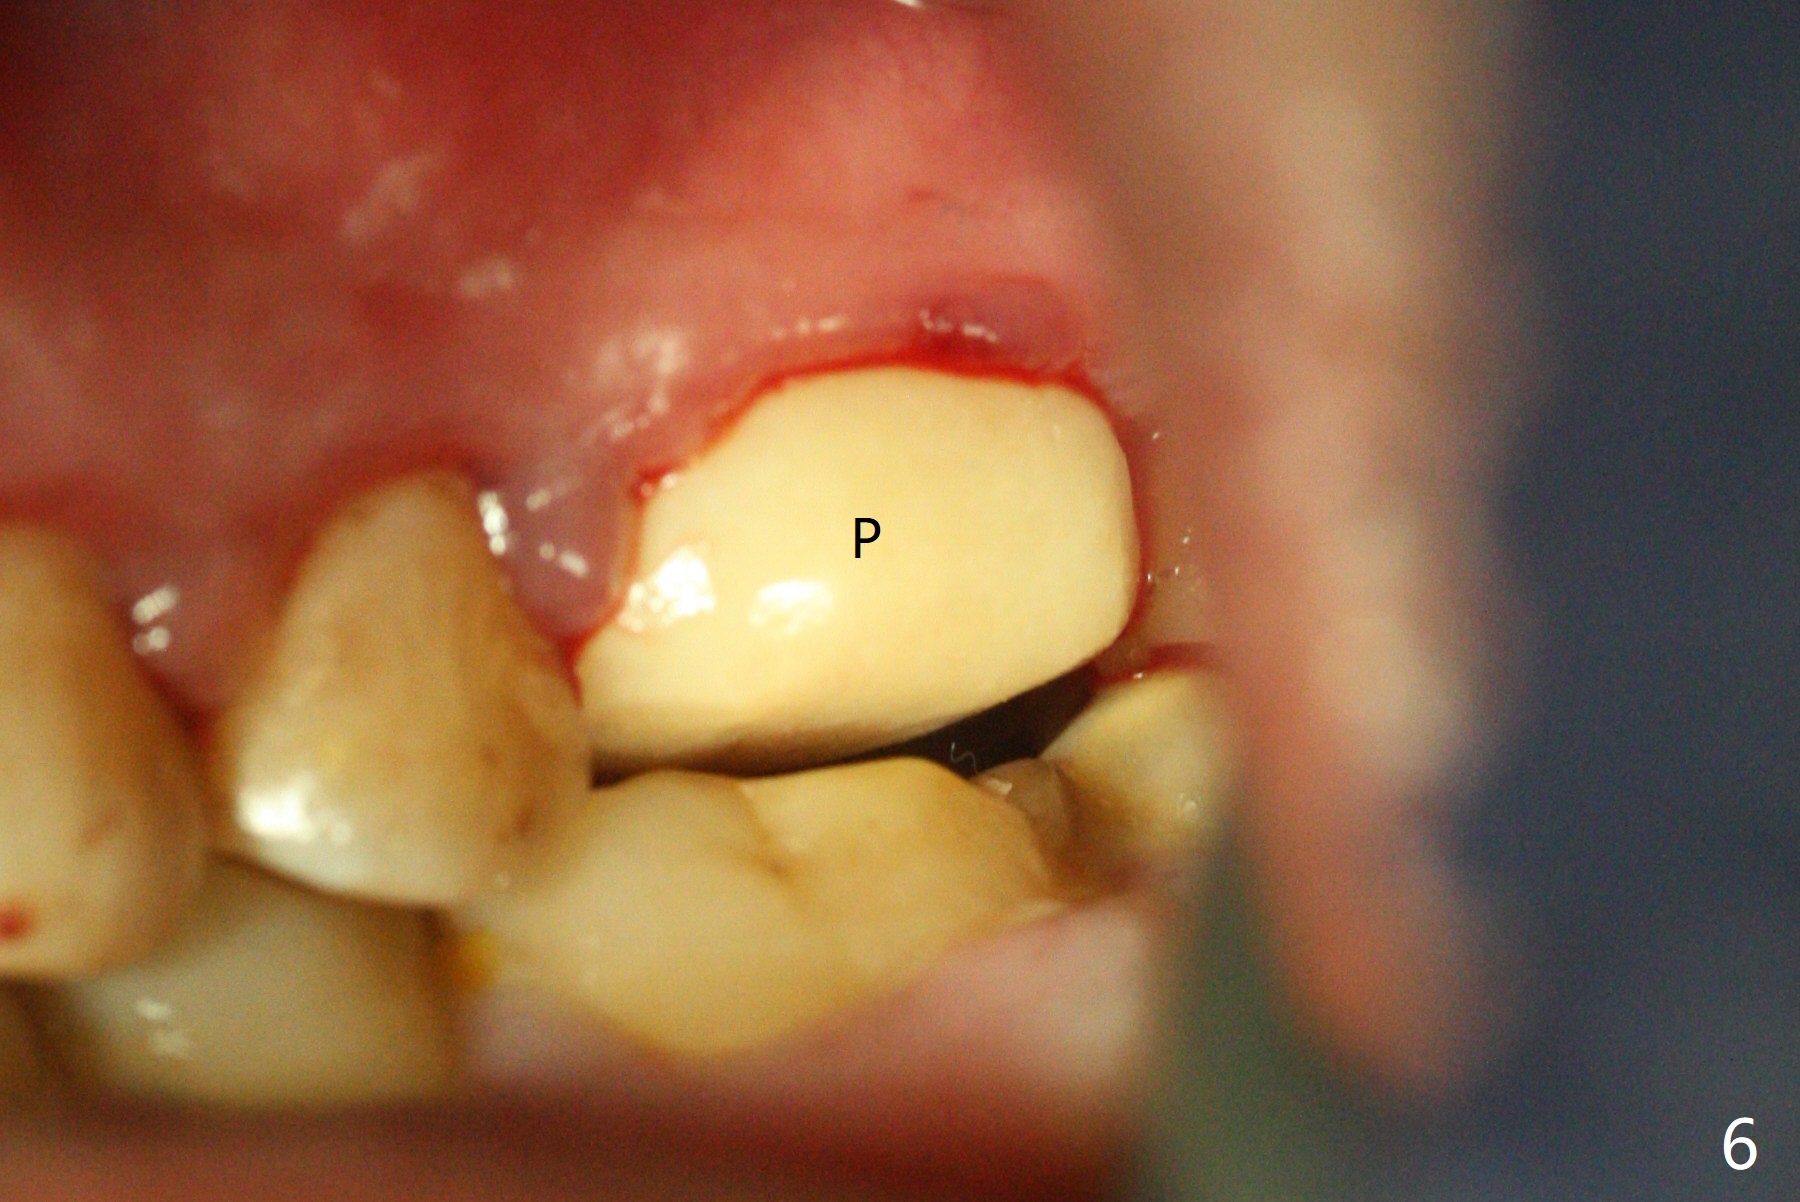

With modification of drill sequence in the last 3 steps (4.5x7.3, 4.0x8.5 and 3.5x10 mm drills) at #14 and sinus lift (Fig.1), a 5x9 mm implant is placed with ~ 50 Ncm following back up twice. Sticky bone mixed with autogenous bone (Fig.1,2 white *) is placed in the sockets before and after placement of a 6.5x5.7(2) mm abutment. Since the palatal gingival margin is recessive (Fig.3 ^), a palatal socket shield retains to prevent further recession (Fig.4 in the end of periodontal probe). Because the margin of the abutment is low, it changes to one with longer cuff (Fig.5). An immediate provisional is fabricated (Fig.6,7 P). The bone graft is indistinguishable from the original alveolus 9 months postop (Fig.8 *). The palatal socket shield is exposed 10 months postop (Fig.9 <). Since the implant is intentionally placed buccal; the sheath is not essential.